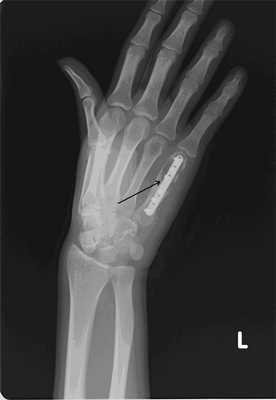

Пациентка Я., 34 года, заметила увеличение области V пястно-фалангового сустава левой кисти, через полгода начали беспокоить боли в данной области. Обратилась в СОКОД, после дообследования была госпитализирована в отделение общей онкологии с диагнозом: энхондрома V пястной кости левой кисти, для оперативного лечения (рис. 2а). Выполнено: экскохлеация очага, обработка образовавшейся костной полости при помощи аргоно-плазменной установки мощностью 60Вт. Аутопластика участком крыла левой подвздошной кости. Остеосинтез пластиной с винтами (рис. 2б). Иммобилизация гипсовой лангетой 6 недель. Пациентка наблюдается в условиях СОКОД в течение года.

| Рис.2. а) Рентгенограмма левой кисти в прямой проекции больной Я. до оперативного лечения (стрелками указана энхондрома V пястной кости). | Рис. 2 б) Рентгенограмма левой кисти в прямой проекции больной Я. после оперативного лечения спустя 3 дня (стрелкой указана зона выполненной операции с наличием металлофиксатора). |